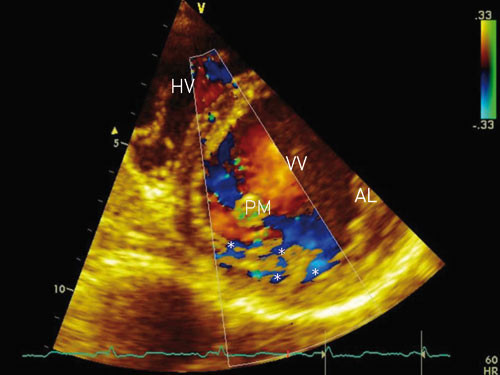

Manglende modning av venstre ventrikkel er rapportert å forekomme hos mindre enn 1 % av pasientene i forskjellige ekkokardiografiske materialer og kan foreligge som familiær disposisjon. Tilstanden er ganske nylig beskrevet som en årsak til dysfunksjon av venstre ventrikkel (1) – (6) og skyldes feil i den endomyokardiale embryogenesen (1). Den kan både hos barn og voksne medføre hjertesvikt, systemiske embolier og/eller ventrikulære arytmier (1, 2, 7) – (9). Diagnosen stilles ved todimensjonal ekkokardiografi eller MR av hjertet (5, 7, 9) – (12). Typisk påvises venstre ventrikkels myokard med et tynnere og normalt utviklet ytre lag, mens det indre laget mot endokard er trabekulært fortykket, med dype intertrabekulære recesser (fig 1).

Under embryogenesen består hjertet av et nettverk av muskelfibre som normalt fortettes, og de intertrabekulære sinusoidene degenerer. Denne myokardmodningen (compaction) foregår i 5. – 8. svangerskapsuke og medfører at de intertrabekulære sinusoidene omdannes til kapillærer. Prosessen starter fra epikard og fortsetter innover til endokard, fra basis av hjertet til apex, og er mer fullkommen i venstre ventrikkel enn i høyre. Samtidig utvikles den koronare sirkulasjonen (1, 13). Ved manglende modning går denne prosessen i stå. Dette resulterer i multiple persisterende og tydelige ventrikulære trabekler og dype intertrabekulære recesser som kommuniserer med ventrikkelkaviteten og ikke med koronarsirkulasjonen (fig 1, fig 2). De intertrabekulære recessene og ventrikkelkaviteten er kledd med sammenhengende endotel (1, 2, 5). Predileksjonssteder for denne manglende modningen, som man ellers finner normalt hos fisker, amfibier og krypdyr (4), er venstre ventrikkels midtre og distale segmenter av laterale og nedre vegg samt apexavsnittet (5, 9, 13). Graden av endringer varierer fra pasient til pasient (1, 4).

Etter hvert har man fått økt kunnskap om patogenese, diagnostikk og prognose, og tilstanden er nylig blitt klassifisert som en primær kardiomyopati (17). Ekkokardiografi eller MR-undersøkelse (12) av hjertet angis som gullstandard for diagnostikk. Flere ekkokardiografiske funn angis som typiske (2, 5, 7, 9) – (11):

fravær av andre hjertemisdannelser (per definisjon).

affeksjon av apex og/eller apikale og/eller midtventrikulære segmenter av nedre og/eller laterale vegg. Mer enn 80 % av pasienter med denne tilstanden har manglende modning på ett eller flere av disse predileksjonsstedene.

tre eller flere uttalte myokardtrabekler vurdert i samme bildeplan.

dype intertrabekulære recesser som kommuniserer med ventrikkelkaviteten.

de affiserte myokardavsnittene er tolaget, bestående av et tynt ytre epikardialt lag og et fortykket trabekulært indre endokardialt lag.

det ytre myokardlaget er fortettet på normal måte, mens det indre laget ikke er fortettet. Ved måling av tykkelsen av veggsegmentene i endesystolen, vil forholdet mellom det ikke-fortettede og det fortettede laget typisk være > 2,0.